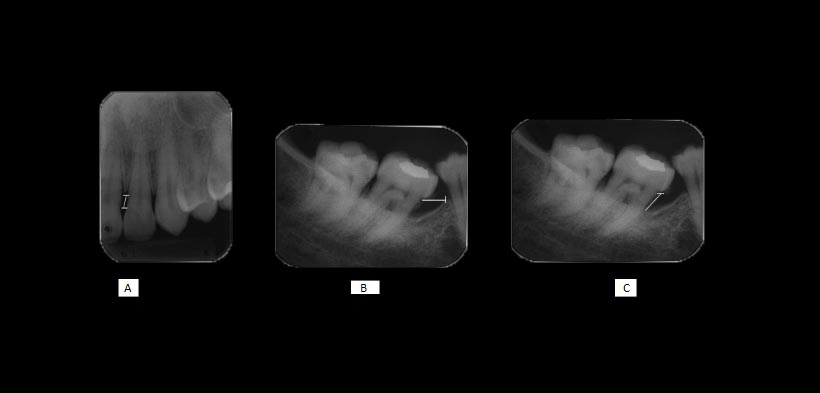

Un parámetro importante para la evaluación de la altura ósea es la distancia que existe entre la cresta del hueso alveolar a la unión del esmalte con el cemento (UCA). En la literatura existen amplias variaciones de la normalidad con respecto a ésta altura, que van desde 1 mm a 3 mm, aunque una distancia de 2 mm es más ampliamente aceptada como normal. En adultos jóvenes, la altura media del hueso en relación con la UCA es 1,4 mm y para las personas mayores de 45 años, este promedio se amplía a 3 mm (fig 1, 2, 3).

Fig 1. Radiografías periapicales que ilustran las distancias: (A) de la unión cemento-esmalte (CEJ) a la cresta alveolar (AC) en las zonas mesial de la pieza 2.2, (B) de la CEJ a la parte inferior del defecto y (C) la anchura del defecto en la superficie mesial de la pieza 4.7 (líneas blancas).